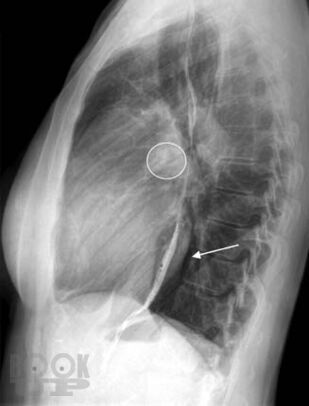

Аннотация

Монография посвящена проблемам диагностики и лечения легочной гипертензии. Термином «легочная гипертензия» объединяют группу нозологий с общим диагностическим критерием — повышением давления в легочной артерии. В работе представлены вопросы патогенеза и генетические основы легочной гипертензии, дана ее современная классификация, описаны формы легочной артериальной гипертензии, легочной гипертензии вследствие патологии левых отделов сердца, легких или хронической тромбоэмболии легочной артерии. Дан диагностический алгоритм, включающий оптимальные методы диагностики. Монография представляет современные возможности лечения легочной гипертензии, знакомит с данными ключевых рандомизированных клинических исследований и позволяет заглянуть в будущее. Работа создана специалистами ведущих экспертных центров нашей страны во главе с ФГБУ «Российский кардиологический научно-производственный комплекс» МЗ РФ и предназначена для кардиологов, пульмонологов, терапевтов, ревматологов, а также для практикующих врачей, имеющих отношение к обследованию и лечению больных с легочной гипертензией.